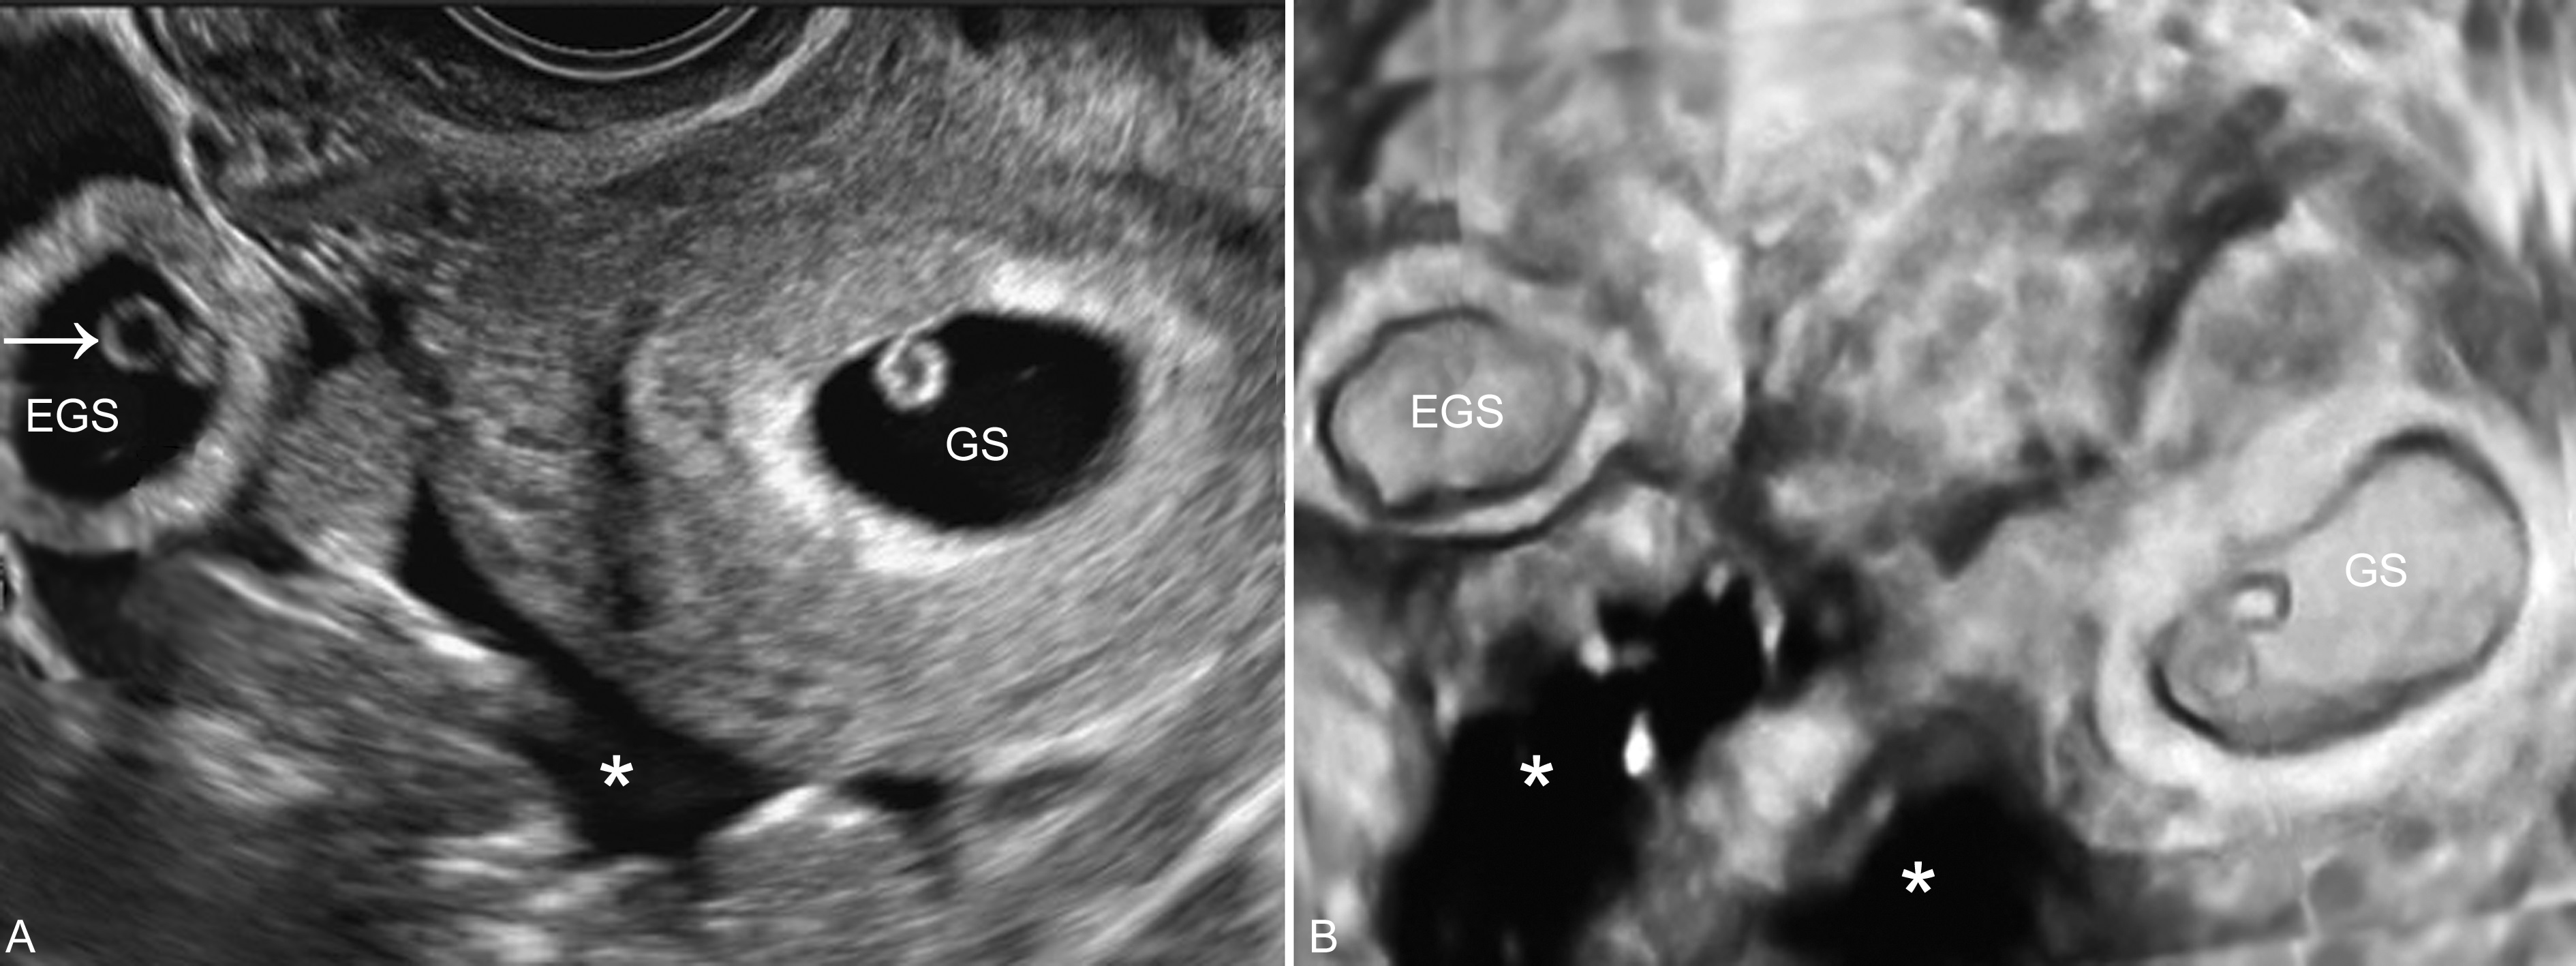

1、子宫增大 在激素的作用下,几乎所有的输卵管妊娠均可引起子宫体积的增大,但大多数小于停经月份;子宫内膜回声增厚,约有10%~20%的患者宫腔内可显示梭形或扁圆形无回声结构(图1,2),称为“假妊娠囊”(false gestational sac)或称为宫腔内积液(intrauterine fluid with ectopic pregnancy)。一般认为,正常的宫内孕囊多位于子宫腔内的一侧,与子宫腔一起形成“双环征”。仔细检查其内部有无卵黄囊及胚胎回声对鉴别宫腔内妊娠和宫腔外妊娠很有价值。部分病人子宫可无明显增大。由于近年来子宫内外同时妊娠的发生率明显增加,当在子宫腔内确定妊娠后,也要仔细检查子宫旁回声,以排除子宫内外同时妊娠的可能。

图7宫内妊娠合并宫外孕腹腔积血